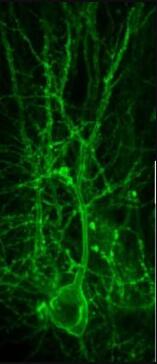

图片来源:Courtesy Zhu Lab, University of Virginia School of Medicine研究者J. Julius Zhu表示,此前我们并没有方法来理解大脑中神经传递的工作机制,就以阿尔兹海默病为例,如今我们花费了数十亿美元,但几乎并没有找到该病有效的疗法,而这项研究中,我们所开发的新方法就能帮助我们第一次看到疾病发生的详细过程。理解神经系统疾病为了能够阐明这种技术的有效性,研究人员利用这种技术对被称之为乙酰胆碱的神经递质进行了可视化研究,乙酰胆碱在机体行为发生过程中扮演着关键角色,因为其会影响大脑的记忆和情绪,同时其也会影响个体患多种疾病的风险,比如阿尔兹海默病、精神分裂症、抑郁症以及所有情绪相关的疾病和精神疾病。乙酰胆碱能够调节胰腺中胰岛素的分泌,并且控制机体压力和血压水平。用来抵御阿尔兹海默病进展的药物能够有效抑制乙酰胆碱酯酶,这种酶类能够降解乙酰胆碱,从而就能够增强大脑中乙酰胆碱释放的效应,目前研究人员并没有完全理解这种药物的作用机制,而且也并没有方法能够确定其所能产生的抑制作用;研究者表示,这些药物或许也并不是很有效,其仅能带来微小的改善作用,而且一旦患者停止服药,其机体疾病的症状就会恶化,因此在治疗这些病人的过程中,你或许会暂时增强药物的用量,但实际上这会让患者的病情更糟。如今研究人员看到了以荧光色标记的乙酰胆碱和其它神经递质的作用过程,临床医生或许就能建立一种健康基线来帮助神经系统疾病患者恢复。最后研究者Zhu表示,我们想要首先测定神经递质正常发挥作用的机制,如今我们发现乙酰胆碱的传递方式或许与我们想象中不太一样,后期我们还将通过更为深入的研究来患者机体中所发生的变化,从而为后期开发治疗多种神经系统疾病的新型疗法提供思路。原始出处:Miao Jing, Peng Zhang, Guangfu Wang, et al. A genetically encoded fluorescent acetylcholine indicator for in vitro and in vivo studies. Nature Biotechnology, 2018; DOI: 10.1038/nbt.4184